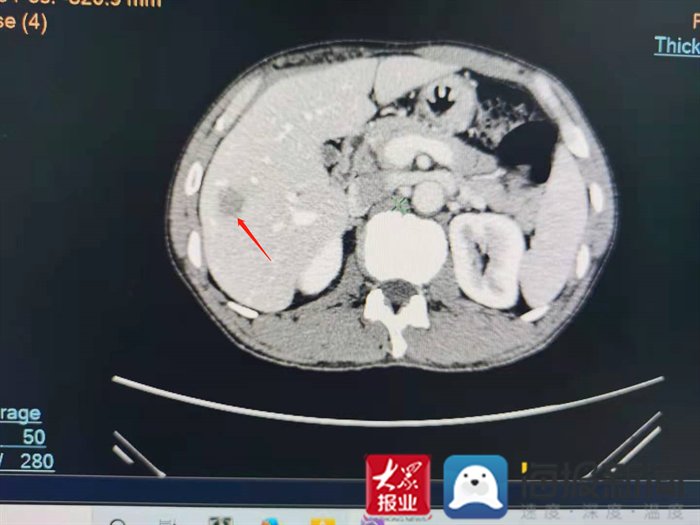

CT显示患者肝右叶S6段见一斑片状低密度灶(红色箭头所示)